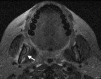

Medication-related osteonecrosis of the jaw (MRONJ) is a rare, severe debilitating condition from unknown causes. It is characterized by nonhealing exposed bone in a patient with a history of antiresorptive or antiangiogenic agents in the absence of radiation exposure to the head and neck region. The first case of MRONJ was reported in the early 2000s. Diagnostic criteria for MRONJ was developed by the American Association of Oral and Maxillofacial Surgeons (AAOMS) based on pharmacological history as well as clinical and radiographic features. Antiresorptive medications such as bisphosphonate and denosumab are currently considered the treatment of choice in patients with osteoclastic bone disease. These reduce bone turnover and improve bone density, thereby improving bone quality. These agents have also been shown to reduce the risk of osteoporotic fractures due to their potent effect in suppressing osteoclastic activity by slowing the remodeling process and increasing bone density, thereby improving quality of life for most of the patients. Despite the great benefits of bisphosphonates and other antiresorptive medications, osteonecrosis of the jaw (ONJ) due to the effects of these medications in the presence of a local risk factor is a significant drawback. Moreover, antiangiogenic drugs play a major role in developing bone necrosis. They are prescribed in cancer cases to prevent metastasis through the blood and lymph nodes. These drugs interfere with the formation of new blood vessels, resulting in ischemia and eventually ONJ. This risk can be managed by evaluating the route and the duration of administration as such a risk can be considered dose-time dependent. As a preventive measure, dental screening before initiating any type of ONJ-related medications can significantly lower the risk of ONJ. Treatment goals can be achieved through pain and infection control, in addition to the management of bone necrosis and resorption. The aim of this review is to identify all causative agents and summarize the preventive measures, diagnostic criteria, and treatment strategies related to MRONJ.

Figures